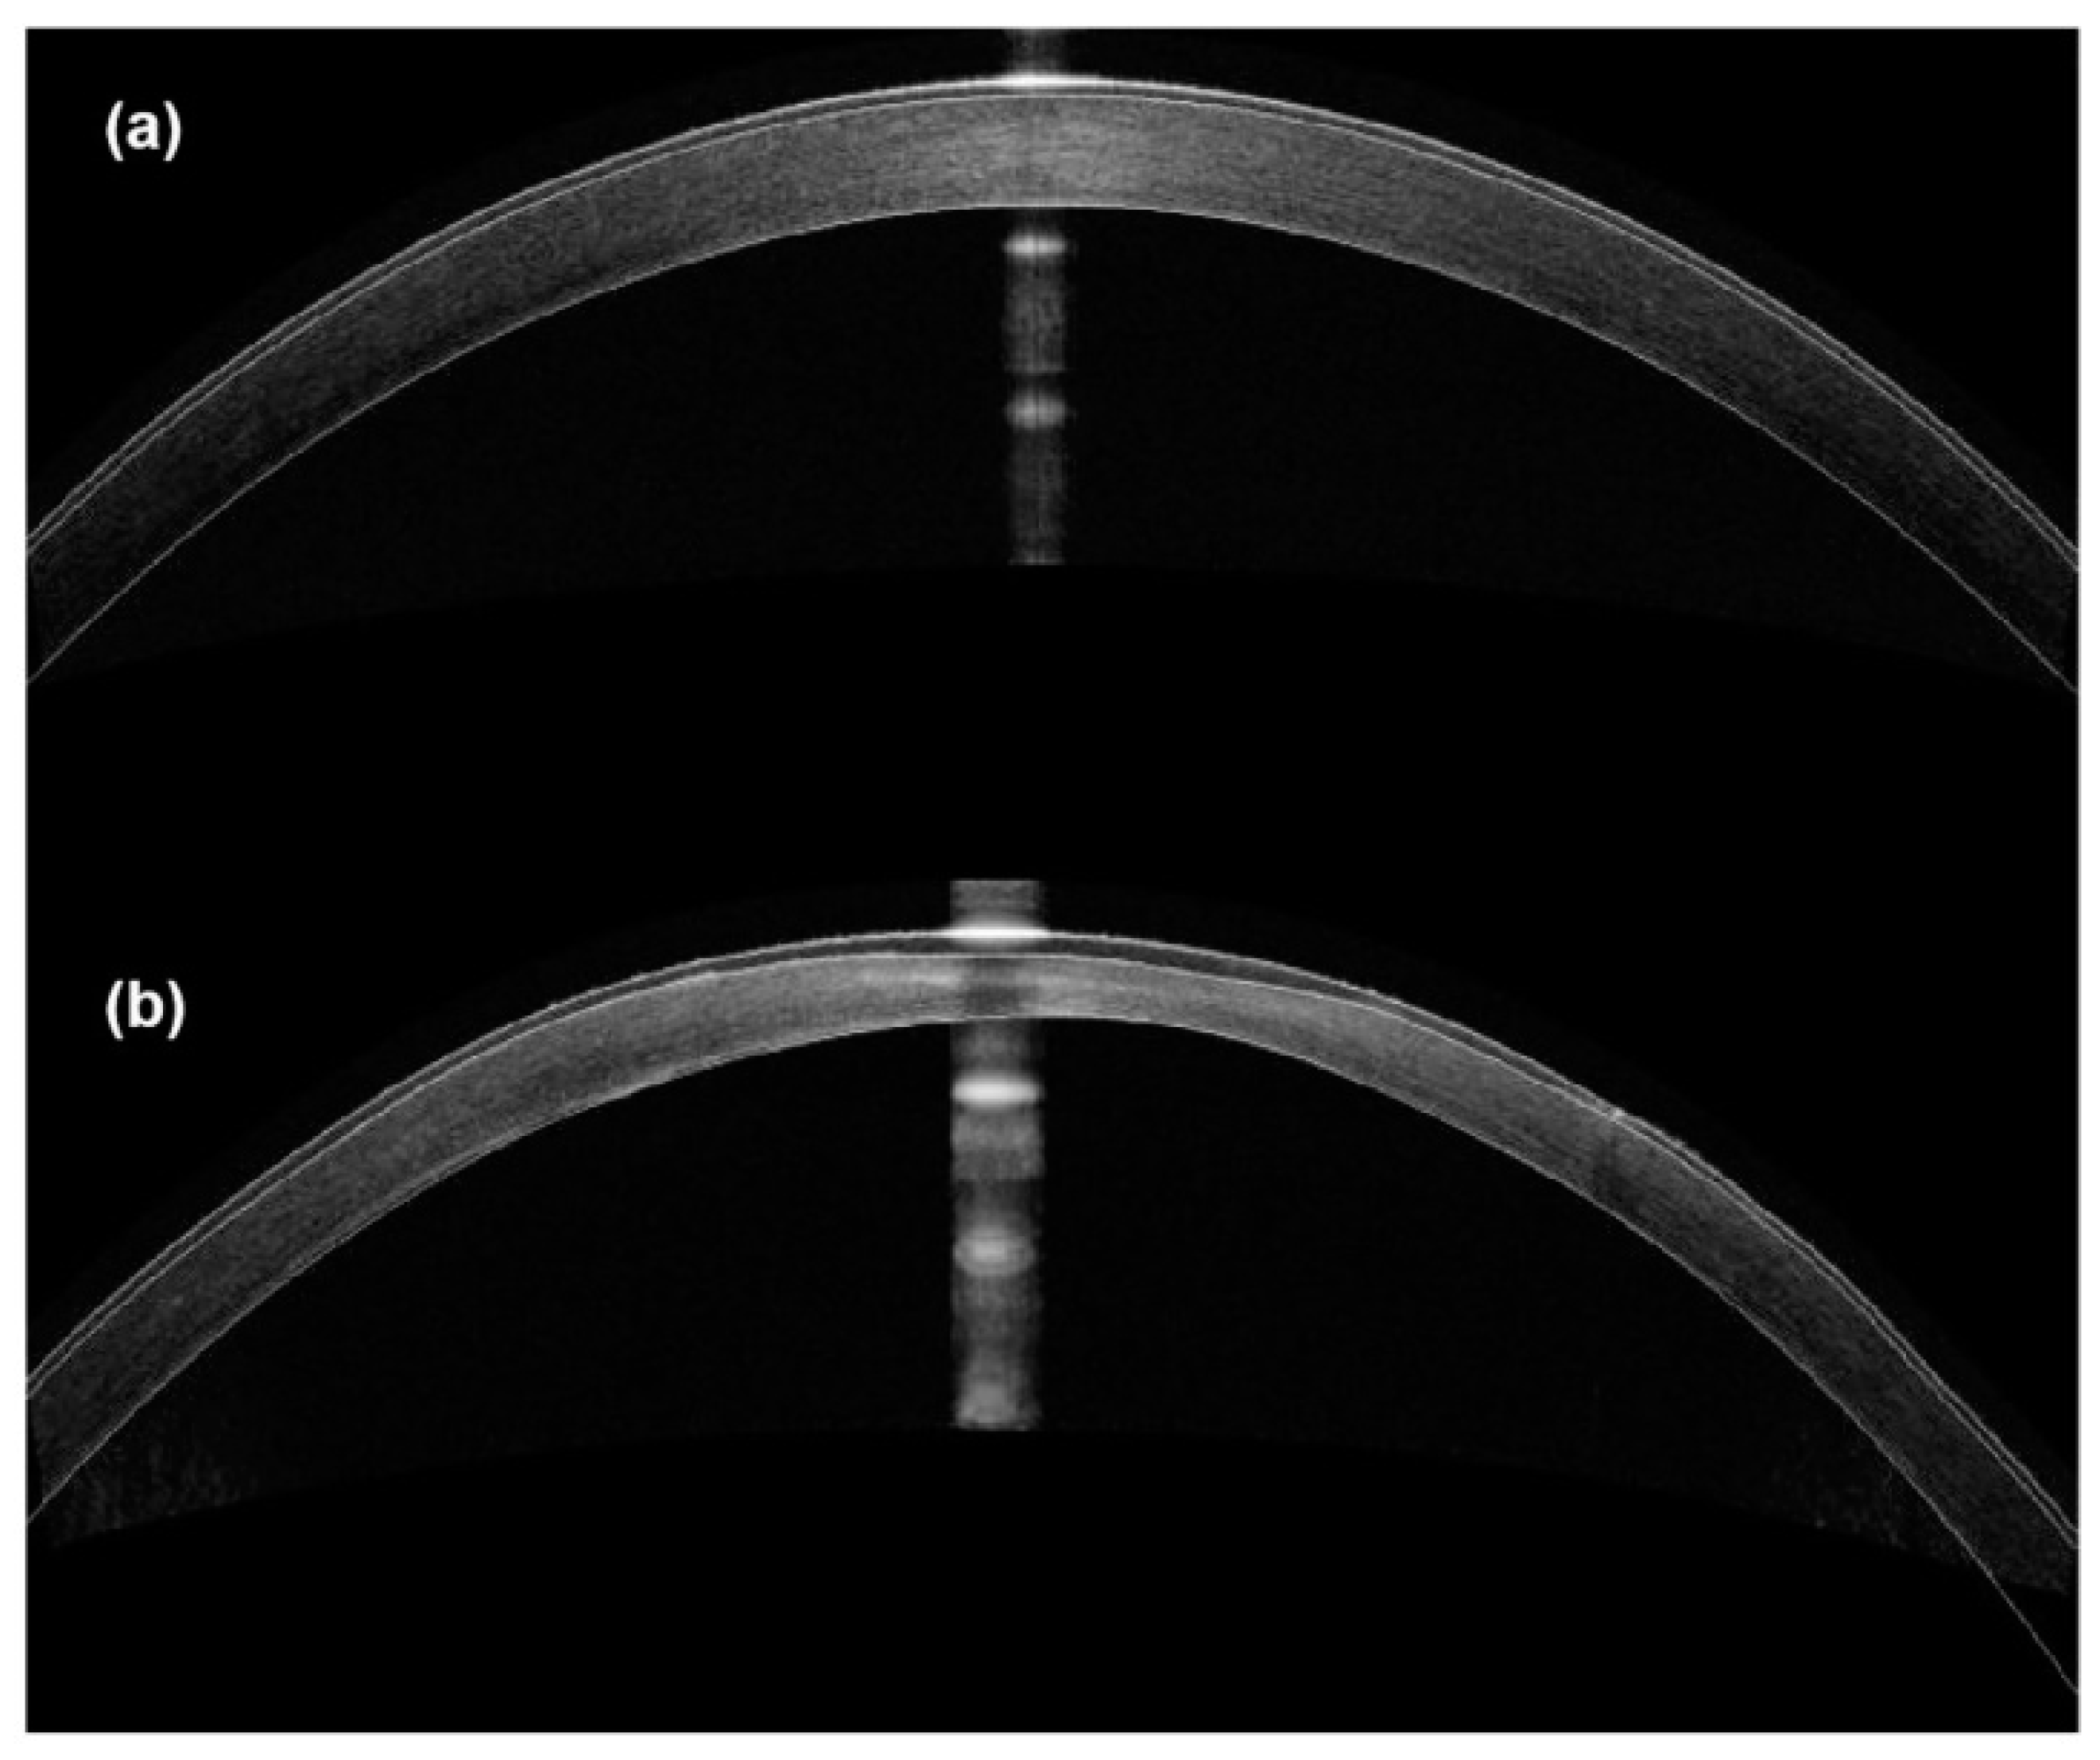

- Qiao, J.; Li, H.; Tang, Y.; Song, W.; Rong, B.; Yang, S.; Wu, Y.; Yan, X. A rabbit model of corneal Ectasia generated by treatment with collagenase type II. BMC Ophthalmol. 2018, 18, 94. [Google Scholar] [CrossRef]

- Wei, J.; He, R.; Wang, X.; Song, Y.; Yao, J.; Liu, X.; Yang, X.; Chen, W.; Li, X. The Corneal Ectasia Model of Rabbit: A Validity and Stability Study. Bioengineering 2023, 10, 479. [Google Scholar] [CrossRef]